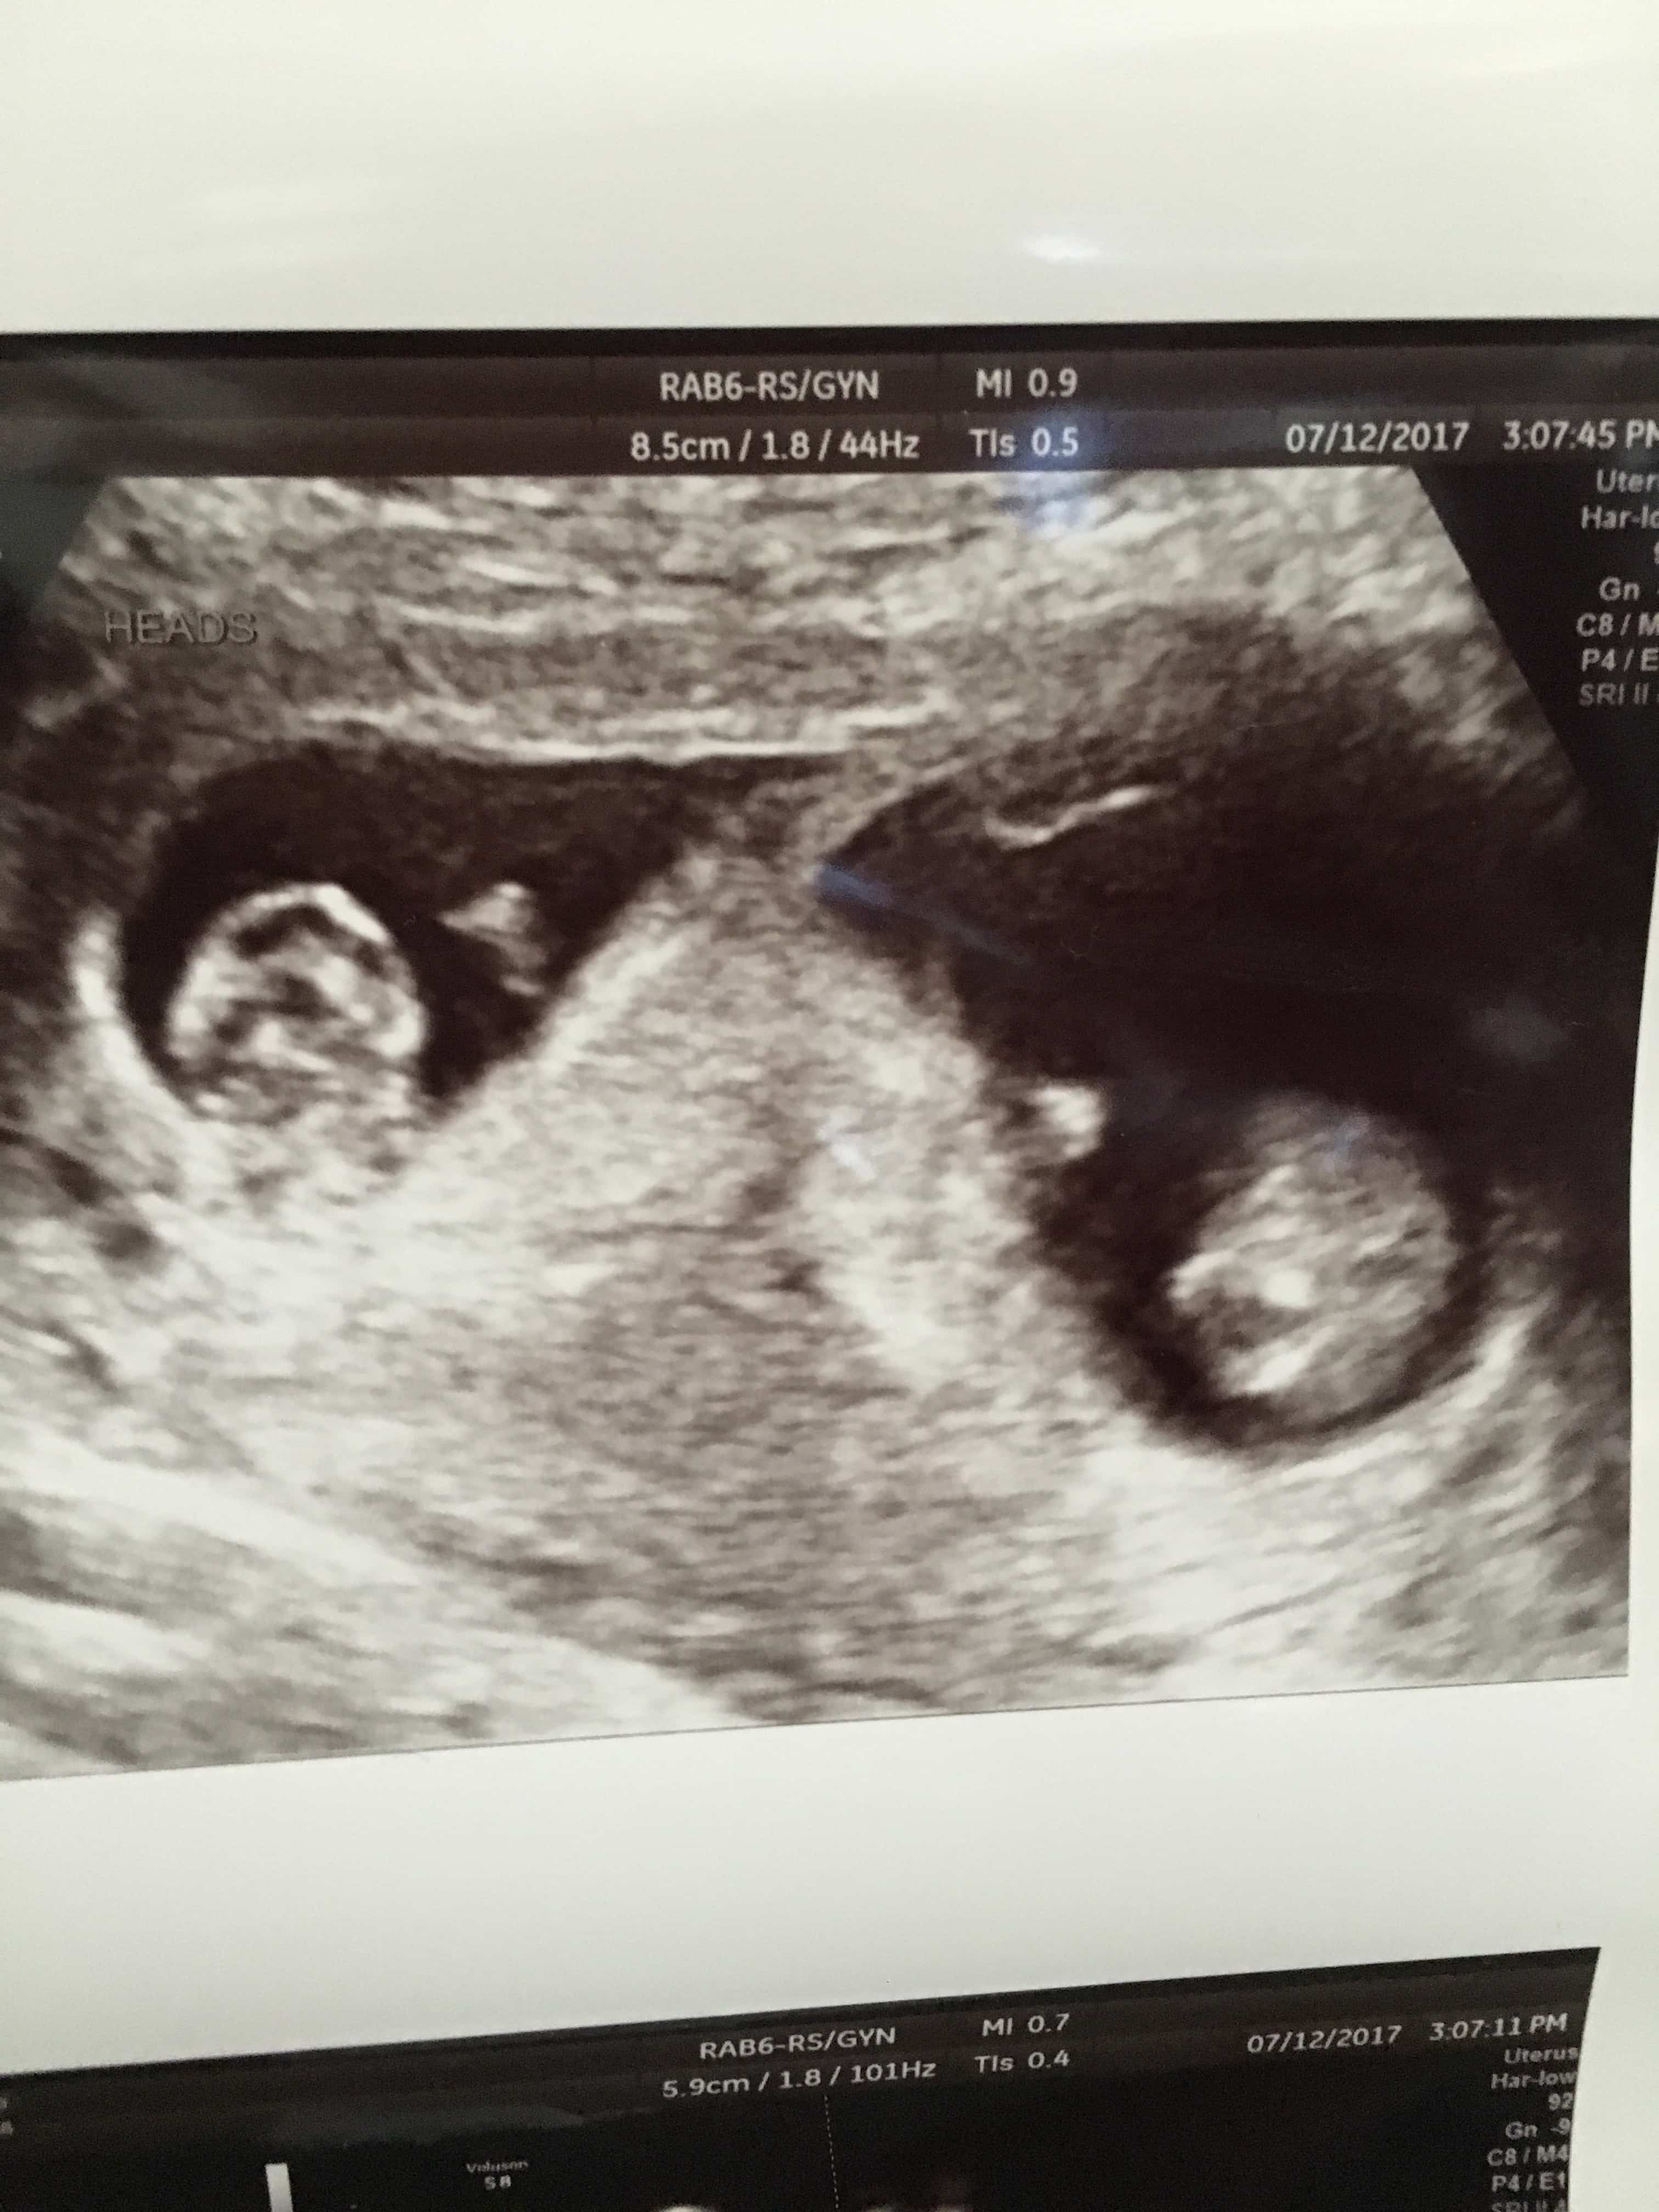

Ultrasound Photos of 9 Weeks Pregnant With Twins